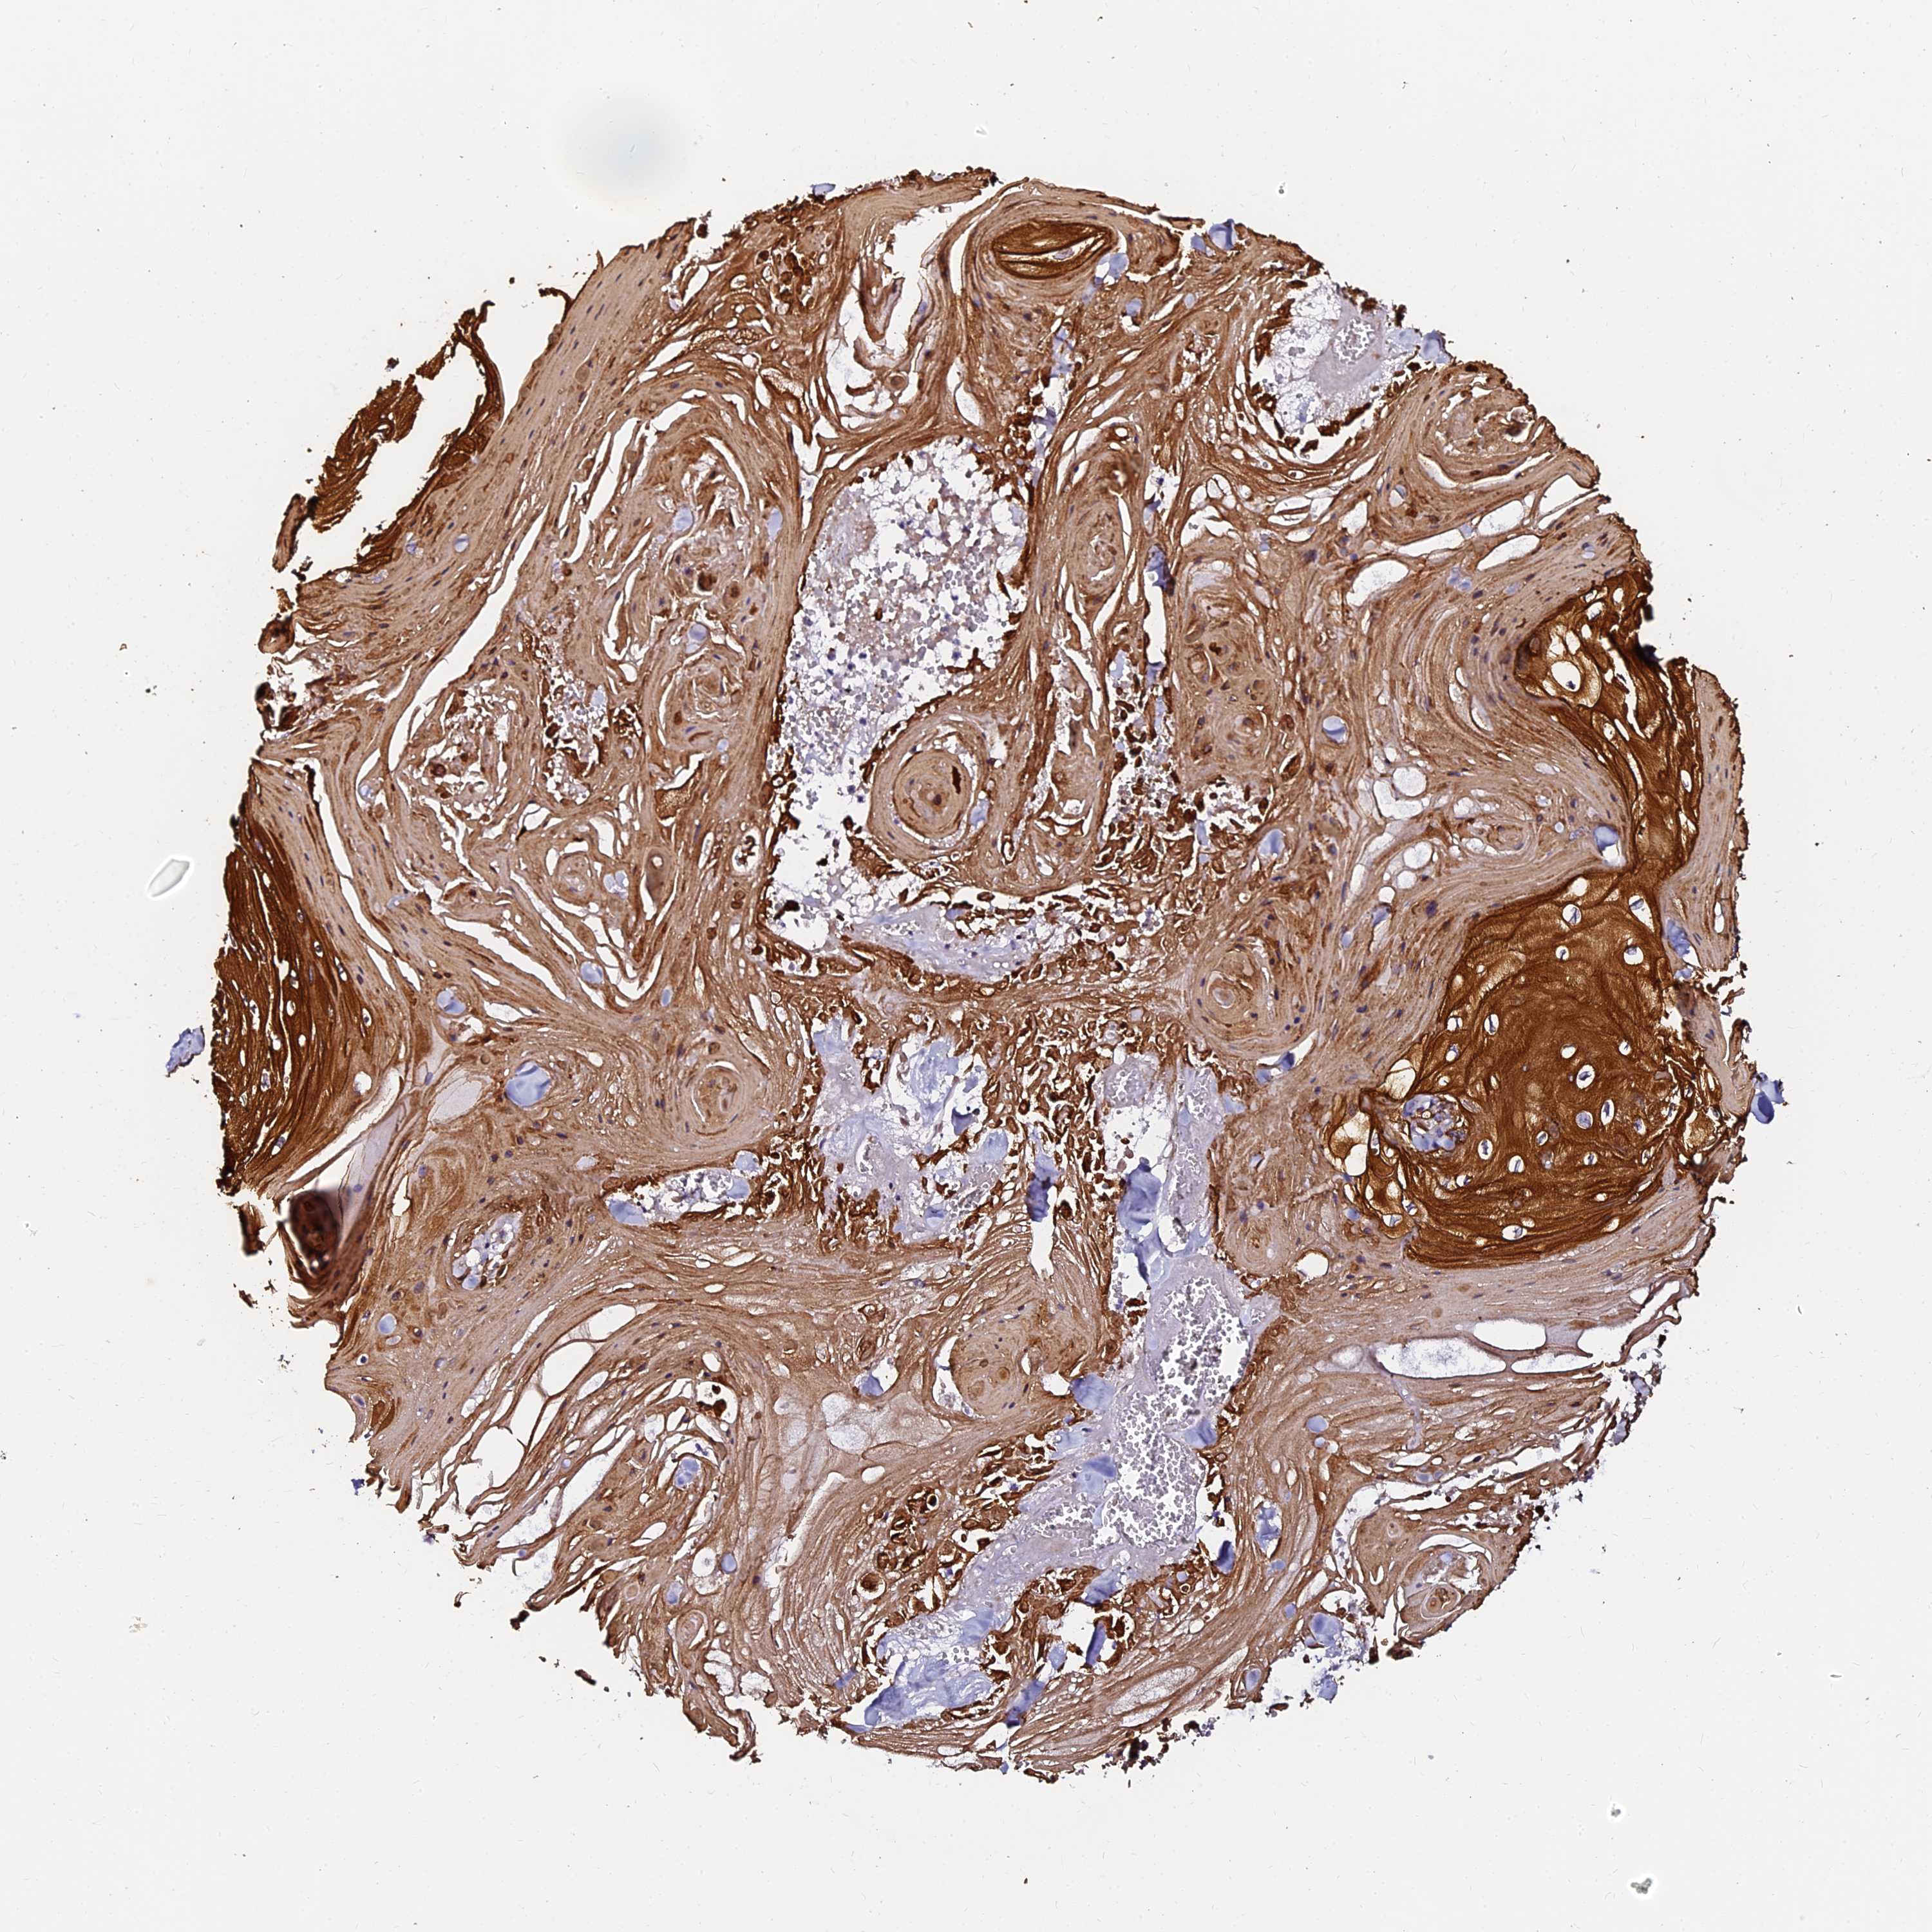

SKIN CANCER - Protein expressioni

A mouse-over function shows sample information and annotation data. Click on an image to view it in a full screen mode. Samples can be filtered based on level of antibody staining by selecting one or several of the following categories: high, medium, low and not detected. The assay and annotation is described here.

Each image is clickable and will lead to virtual microscopy that enables deeper exploration of all samples and also displays staining intensity scores, fraction scores and subcellular localization as well as patient and tissue information for each sample.

Antibody HPA039764

Staining

High

Intensity

Strong

Quantity

>75%

Location

Nuclear

Basal cell carcinoma

Squamous cell carcinoma, NOS

Squamous cell carcinoma, metastatic, NOS

Squamous cell carcinoma in situ, NOS